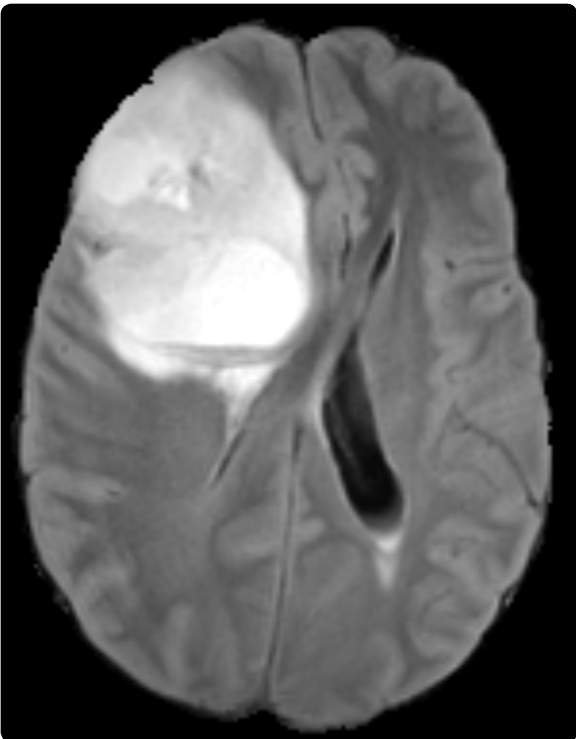

[A slice of the T1 image]

[A soft mask slice]

[Spaghetti plots of thresholded soft masks]

[3D contour boxplots]

5.1 Brain MRI Segmentation Soft Masks

Our method is applied to ensembles of soft masks from a collection of segmentation models as shown in Fig.˜8. We use a 3D brain tumor MRI dataset (T1/T1ce/T2/FLAIR) MSD Tumour [antonelli2022medical] with voxel-wise labels for four classes (background, necrotic/non-enhancing core, edema, enhancing tumor) as shown in Fig.˜8(a).The data has a spatial resolution of voxels. For the ensemble input to PID-mean, we train 31 SegResNet models under different initialization and training-stabilization configurations while keeping the architecture and augmentations fixed, then collect the soft mask outputs (one exemplary soft mask is shown in Fig.˜8(b)) of these 31 models on the same test data (Fig.˜8(c)). Details of the data preparation are covered in the supplemental material [supplemental:ProbInclDepth].

Contour boxplots of 3D soft mask ensembles (thresholded by a probability of 0.5 to create surfaces) sorted by PID-mean are visualized in Fig.˜8(d). The refractions highlight the fine details of the complex shapes of the brain tumor. It can be seen that the envelopes of 50% members (orange) and 100% (blue) members are largely identical but differ in several locations on the outer boundaries, while the median member (yellow) is inside of the band of 50% members. Note that due to color blending, the inner surface of the 100% members band in blue appears light emerald green, and this holds for other examples in the Section too.

The contour boxplot can help with segmentation quality control for soft masks. Low-depth contours identified by PID-mean can effectively flag high-risk or outlier segments for review. Whereas high-depth contours indicate the typical segment from the collection of segmentation networks. By further examining the associated soft masks, one can improve the settings of the segmentation model for desired results.